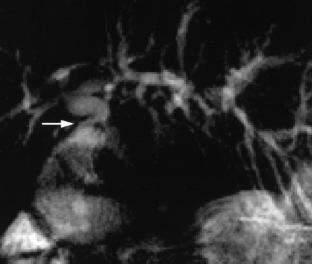

Usual and unusual causes of extrahepatic cholestasis: assessment with magnetic resonance cholangiography and fast MRI

Cholestasis may result from hepatocellular (intrahepatic) disease or biliary tract (extrahepatic) abnormalities. Etiologies causing extrahepatic cholestasis are extremely diverse and invasive procedures, such as endoscopic retrograde cholangiopancreatography (ERCP) and percutaneous transhepatic cholangiography (PTC), were previously required to establish the diagnosis. Due to refinements of magnetic resonance imaging (MRI) techniques, the patient with extrahepatic cholestasis currently can be evaluated noninvasively, and the information revealed frequently exceeds the findings obtained by ERCP and PTC. In this essay, we illustrate the classic MR cholangiographic (MRC) and MRI features of a variety of disorders causing extrahepatic cholestasis, including non-neoplastic disorders of the biliary tract (congenital abnormalities, infectious processes, iatrogenic disorders, and postsurgical complications) and neoplastic conditions (e.g., tumors of the pancreas, biliary tree, liver, ampulla, and regional lymph nodes). In most cases, familiarity with the key MRC features in addition to information obtained via cross-sectional MR images provide sufficient information for adequate lesion characterization.